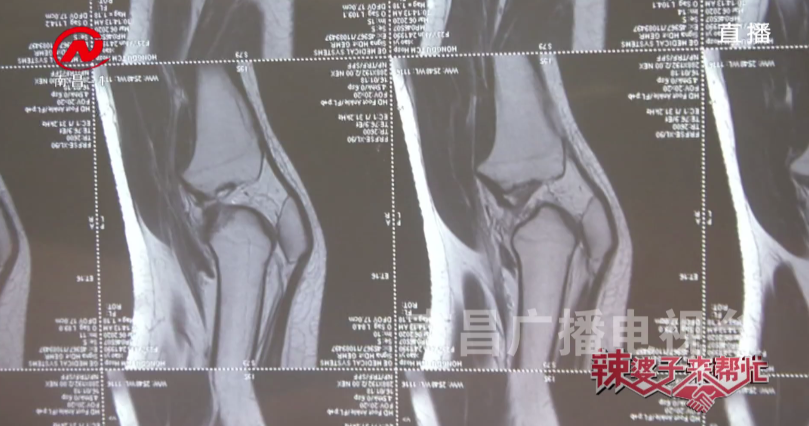

诊断结果为

双膝关节腔及髌上囊少量积液

医生建议肖女士不能再进行运动训练。